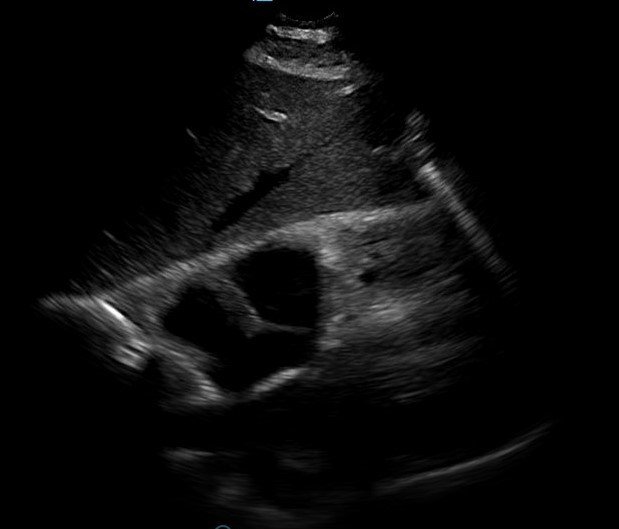

Bedside echocardiogram was performed, which revealed a free-floating thrombus in the right atrium on the sub-xiphoid view as seen in the video. The right atrium is denoted by the blue circle, in which a hyperechoic mobile mass can be seen. This finding was confirmed by an official echocardiogram which shows the thrombus in the right atrium extending through the tricuspid valve, as shown in the second image denoted by the red arrow. Significant right heart strain was also found, with severe pulmonary hypertension and intraventricular septal flattening.